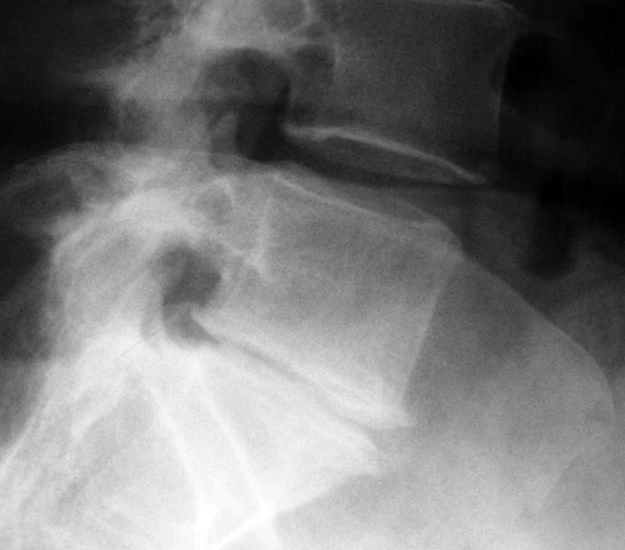

A free medical education seminar series for everyoneA FREE spine education seminar series for everyone Back pain has many faces and to many people it can be distressing, disabling or even frightening. Whether back pain comes from a strain, degenerative disc disease, a herniated disc, spinal stenosis, spondylolisthesis, a complex deformity or even a fracture, there are many options that can help you to live an active lifestyle. Additionally, osteoporosis is another disease that you may not even know you have. Learn from these dynamic experts about the various types of back problems and the latest treatments available. We will discuss the problems, the solutions and leave time for your questions to help you be active. Talk with the experts and get your concerns addressed. Spine Program